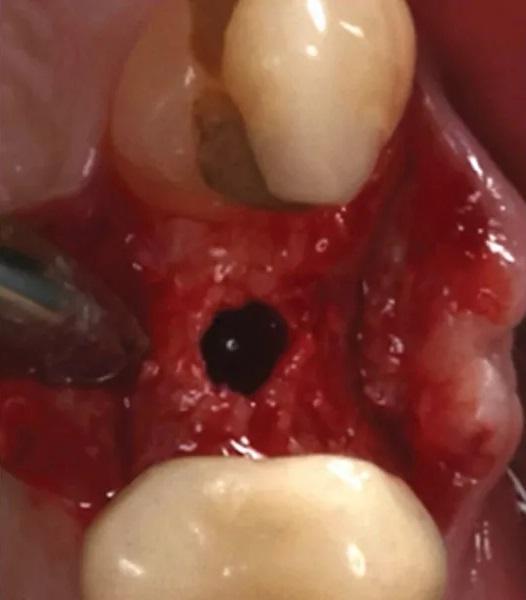

Фото 8. Вестибулярный лоскут слегка отслоен, видны хороший уровень васкуляризации и немедленное образование кровяного сгустка в лунке.

Фото 9. Пробка из ксеногенно-аллопластического биоматериала помещена в лунку, и наложен матрацный шов из ПТФЭ.

Существующая реставрация (№ 2.4) была разделена для получения доступа к фуркации. Оба корня (щечный и небный) были удалены с использованием периотомов, элеваторов и щипцов. Лунка была очищена от грануляционной ткани, которая отправлена на гистопатологический анализ. ПА рентгеновский снимок подтвердил полное удаление корней. Процедура САГ была выполнена с использованием упомянутого выше резорбируемого ксеногенно-аллопластического биоматериала (OsteoGen Plug), который был адаптирован в лунку (Фото 6). ПА рентгеновский снимок подтвердил правильное размещение биоматериала. Участок был ушит швом из политетрафторэтилена (ПТФЭ) (Фото 7 – Фото 10). Пациенту были даны инструкции по гигиене полости рта и послеоперационному уходу.